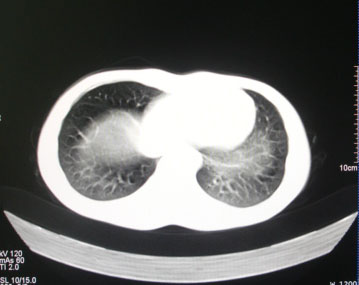

标题: CT26938:单发肺窗

病人17岁。咳嗽伴血丝痰2年?外院x片示左上肺椭圆形影,疑胸腺瘤

左上纵隔占位性病变?

(请补传纵隔窗)